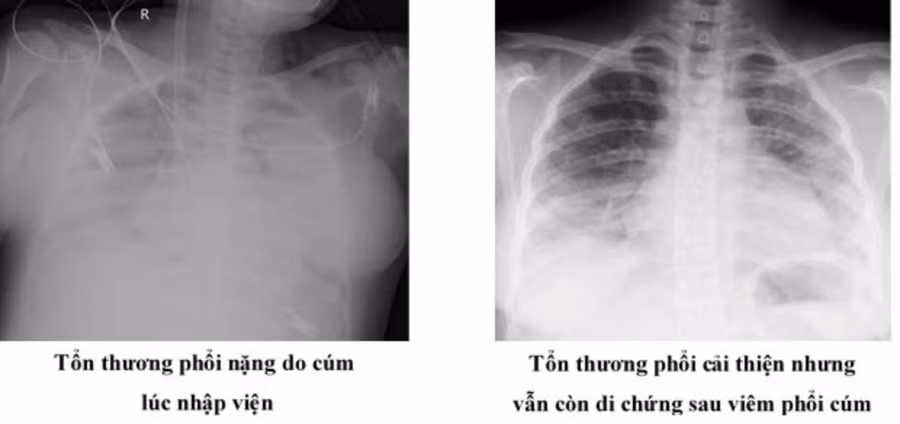

Chủ quan không đi khám vì nghĩ cảm lạnh thông thường, 4 ngày sau, sản phụ N. cảm thấy khó thở, sốt cao, nên đến Bệnh viện Nhân dân Gia Định khám và nhập viện. Trong vòng chưa đến 12 giờ sau nhập viện, sản phụ N. suy hô hấp tiến triển rất nhanh, tổn thương đông đặc gần 80% nhu mô phổi.

ThS.BS Trần Thanh Nam, Khoa Hồi sức tim mạch - Bệnh viện Nhân dân Gia Định, đánh giá, sản phụ N. nhập viện trong bệnh cảnh rất nặng, hội chứng nguy kịch hô hấp cấp với tổn thương nhu mô phổi hai bên gần như hoàn toàn và kết quả xét nghiệm dịch tiết phế quản dương tính với cúm A.